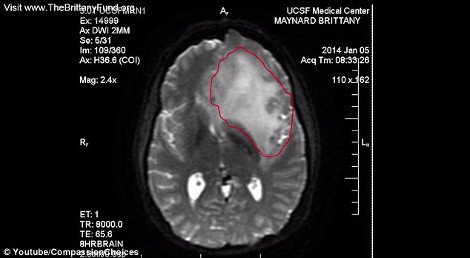

Η ζωή έπαιξε άσχημο παιχνίδι στην 29χρονη Μπρίτανι Μέιναρντ, καθώς, λίγο πριν κλείσει τα 30 της χρόνια διαγνώσθηκε με επιθετική μορφή καρκίνου στον εγκέφαλο.Αποφάσισε, λοιπόν, να βάλει τέλος στη ζωή της γιατί, όπως δηλώνει, θέλει να πεθάνει με αξιοπρέπεια, ενώ, αυτό θα συμβεί με ευθανασία την 1η Νοεμβρίου.

Οι γιατροί της είπαν ότι έχει μόνο έξι μήνες ζωής και πως ο θάνατός της θα είναι αργός και επίπονος και για το λόγο αυτό η Μπρίτανι θέλησε να κάνει ευθανασία.